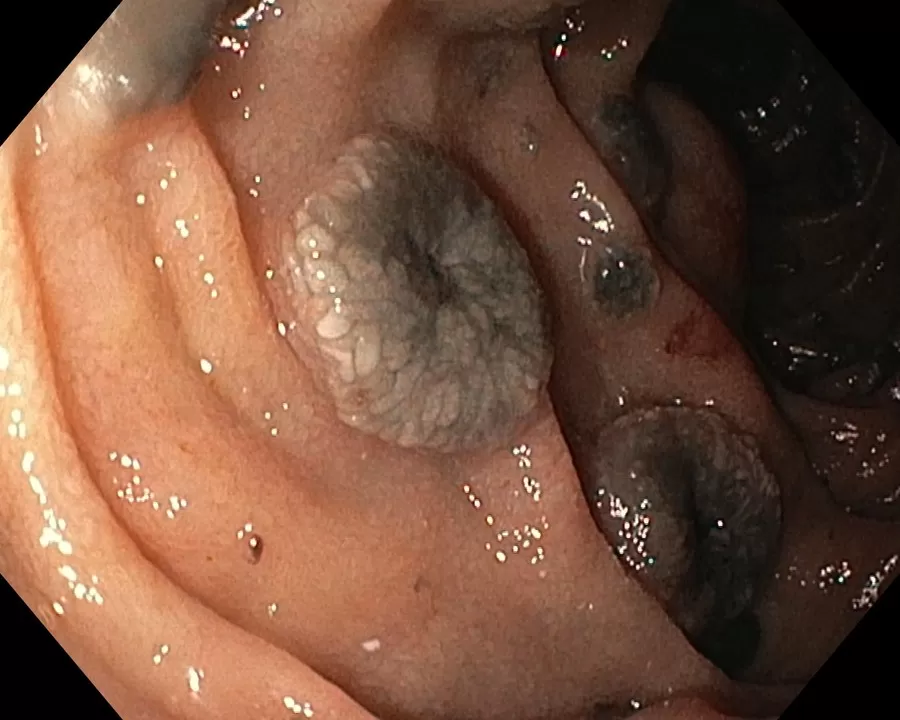

Эзофагогастродуоденоскопия диагностическая

Olympus EVIS EXERA III GIF- H185

12-кишка: Просвет луковицы двенадцатиперстной кишки обычный, содержит небольшое количество желчи, перистальтика активная , слизистая оболочка розового цвета, ворсинки сохранены. Так же прослеживаются пигментированные образования от 2мм до 8мм. серо-синюшного оттенка. Постбульбарном отделе множественные пигментые образования до 10мм, единичные кратообразные пигментные образования до 15мм, глубиной до 5мм., дно покрыто серым фибрином. Биопсия 2-а кусочка.

Заключение: ГПОД. Грыжевая гастропатия. Эрозивная гастропатия антрального отдела желудка. MTS Меланома ЛДПК, залуковичного отдела. Биопсия.